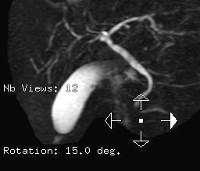

КТ желчных протоков. Это метод диагностики радиации, который используется для изучения желчных протоков и желчного пузыря. Данная методика позволяет изучать долевые желчные протоки печени, общий печеночный проток, желчный пузырь и пузырный проток, холедох, а также общую структуру и размеры печени. КТ желчных протоков позволяет идентифицировать камни, их количество, точное местоположение, размер и степень заполнения канала; воспалительные изменения, нарушения развития, травматические повреждения и региональные раковые заболевания. Как правило, КТ желчных протоков выполняется с улучшенным контрастом. Нативный тест используется для полного заполнения или непереносимости пациента рентгеноконтрастных препаратов.

Сердцем КТ желчных протоков является использование рентгеновских лучей. Компьютерный томограф пропускает небольшое количество излучения через исследуемый участок организма и одновременно восстанавливает его взаимодействие с внутренней тканью. Последние отображаются на томограммах в виде светлых или темных областей. Обработка данных происходит на разных этапах прохождения излучения через тело, что позволяет получить серию слоев для слоистых изображений. Несмотря на то, что компьютерная томография не была введена в медицину до 1980-х годов, КТ-исследование желчных протоков в Москве и других городах Российской Федерации в настоящее время является довольно сложной диагностической процедурой. Это способствует получению высокодетализированных изображений и минимальному количеству искажений и артефактов.